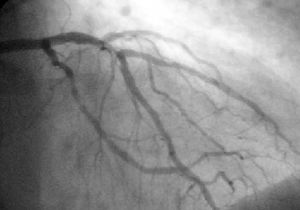

قسطرة الشريان التاجي هي واحدة من العديد من الاختبارات والإجراءات التشخيصية لأمراض القلب . على وجه التحديد ، قسطرة الشريان التاجي هي اختبار مفسر بصريًا للتعرف علي انسداد ، تضيق ، عودة التضيق ، تخثر أو تمدد تجاويف الشريان التاجي ; حجم غرفة القلب; أداء انقباض عضلة القلب ; وبعض جوانب وظيفة صمام القلب . قيم ضغط مهمة كضغط الدم الداخلي للقلب و الرئة لا يمكن قياسه من خارج الجسم،, يمكن قياسها بدقة من خلال هذا الاختبار. المشاكل ذات الصلة التي تتعامل مع اختبار الأكثر شيوعا يحدث نتيجة متقدمة تصلب الشرايين - عصيدة النشاط داخل جدار الشريان التاجي الشرايين . في كثير من الأحيان ، تكون مشاكل الصمامات أو عضلة القلب أو اضطراب نظم القلب هي المحور الأساسي للاختبار .

أثناء قسطرة الشريان التاجي (غالبًا ما يشار إليها باسم القسطرة من قبل الأطباء) ، يتم تسجيل ضغط الدم وتسجيل الكشف الفلوري ( صورة الأشعة السينية المتحركة ) - جرامات الظل من الدم داخل الشرايين التاجية . من أجل إنشاء صور الأشعة السينية ، يوجه الطبيب جهازًا صغيرًا يشبه الأنبوب يسمى القسطرة ، عادةً ~ 2.0 مم (6-فرنسي) في القطر عبر الشرايين الكبيرة بالجسم حتى يصبح طرفها داخل فتحة أحد الشرايين التاجية . حسب التصميم ، تكون القسطرة أصغر من تجويف الشريان الذي توضع فيه ؛ يتم مراقبة ضغط الدم الداخلي (داخل الشرايين) من خلال القسطرة للتحقق من أن القسطرة لا تمنع تدفق الدم

تم تصميم القسطرة نفسها لتكون ظليلة اشعة من أجل الرؤية وتسمح بحقن عامل تباين إشعاعي واضح مائي ومتوافق مع الدم ، يُطلق عليه عادةً صبغة الأشعة السينية ، بشكل انتقائي وخلطه مع الدم المتدفق داخل الشريان. عادةً ما يتم حقن 3-8 سم مكعب من عامل التباين الإشعاعي لكل صورة لجعل تدفق الدم مرئيًا لمدة 3-5 ثوانٍ حيث يتم تصريف عامل التباين الراديوي سريعًا بعيدًا في الشعيرات الدموية التاجية ثم الأوردة التاجية. بدون حقن الصبغة بالأشعة السينية ، يظهر الدم وأنسجة القلب المحيطة ، على الأشعة السينية ، على أنها كتلة كثافة مائية متغيرة بشكل طفيف ، أو كتلة منتظمة من كثافة الماء ؛ لا توجد تفاصيل واضحة عن الدم وبنية الأعضاء الداخلية. يسمح التباين الإشعاعي داخل الدم بتصور تدفق الدم داخل الشرايين أو غرف القلب ، اعتمادًا على مكان الحقن.

إذا كانت عصيدة ، أو جلطات ، بارزة في التجويف ، مما يؤدي إلى تضييق ، فقد يُنظر إلى التضييق بدلاً من ذلك على أنه ضبابية متزايدة داخل صور ظل الأشعة السينية لعمود الدم / الصبغة داخل ذلك الجزء من الشريان ؛ هذا بالمقارنة مع المناطق المجاورة ، التي يُفترض أنها أكثر صحة ، وأقل تضيقًا .

انظر إلى الرسم التوضيحي أحادي الإطار لصورة تصوير الأوعية التاجية في صفحة توسيع الاوعية الدموية.